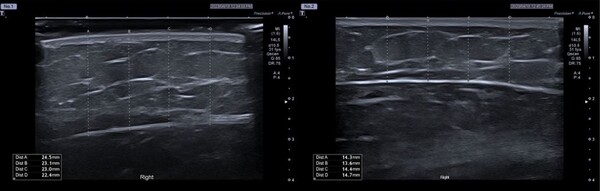

연구팀은 브이올렛 5㎎/㎖, 2.5㎎/㎖를 팔뚝 부위에 8주간 3차례 시술하고 20주간 관찰한 결과, 피하지방 두께가 각각 평균 7.49㎜, 4.68㎜ 감소했다고 밝혔다. 상완 팔둘레 길이 역시 20주 시점에 각각 평균 1.55㎜, 1.1㎜ 감소한 것으로 나타났다.